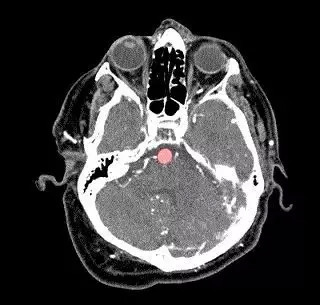

吴恩达团队的研究工具主要是围绕一种名为HeadXNet的算法构建,经过大量训练建立数据后,HeadXNet算法能够确定扫描的每个体素是否存在动脉瘤,其水平相当于在包含动脉瘤的100次扫描中发现另外六个动脉瘤,并将算法的结论以半透明的高亮显示在扫描的顶部。

这种算法决策的表示形式,使得临床医生在没有HeadXNet输入的情况下仍然可以很容易地看到扫描结果,并可以将动脉瘤的确切位置标记给临床医生看,有效提高医生的临床表现。

在此次研究中,八名临床医生通过评估一组115个动脉瘤的脑部扫描对HeadXNet进行了测试,一次是在HeadXNet的帮助下进行的,一次没有。通过该工具,临床医生正确识别出了更多的动脉瘤,从而降低了“漏诊率”,而且医生之间更有可能达成一致。此外,HeadXNet并没有影响临床医生决定诊断所需的时间,也没有影响医生在患者没有动脉瘤的情况下正确识别扫描的能力。